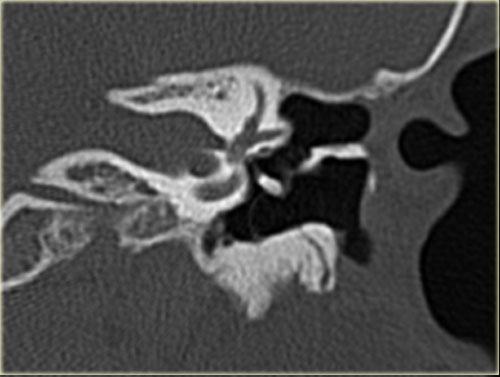

Bên trái là các hình ảnh mặt phẳng coronal của cùng bệnh nhân trên.

Lưu ý cholesteatoma đã ăn mòn scutum (mũi tên).